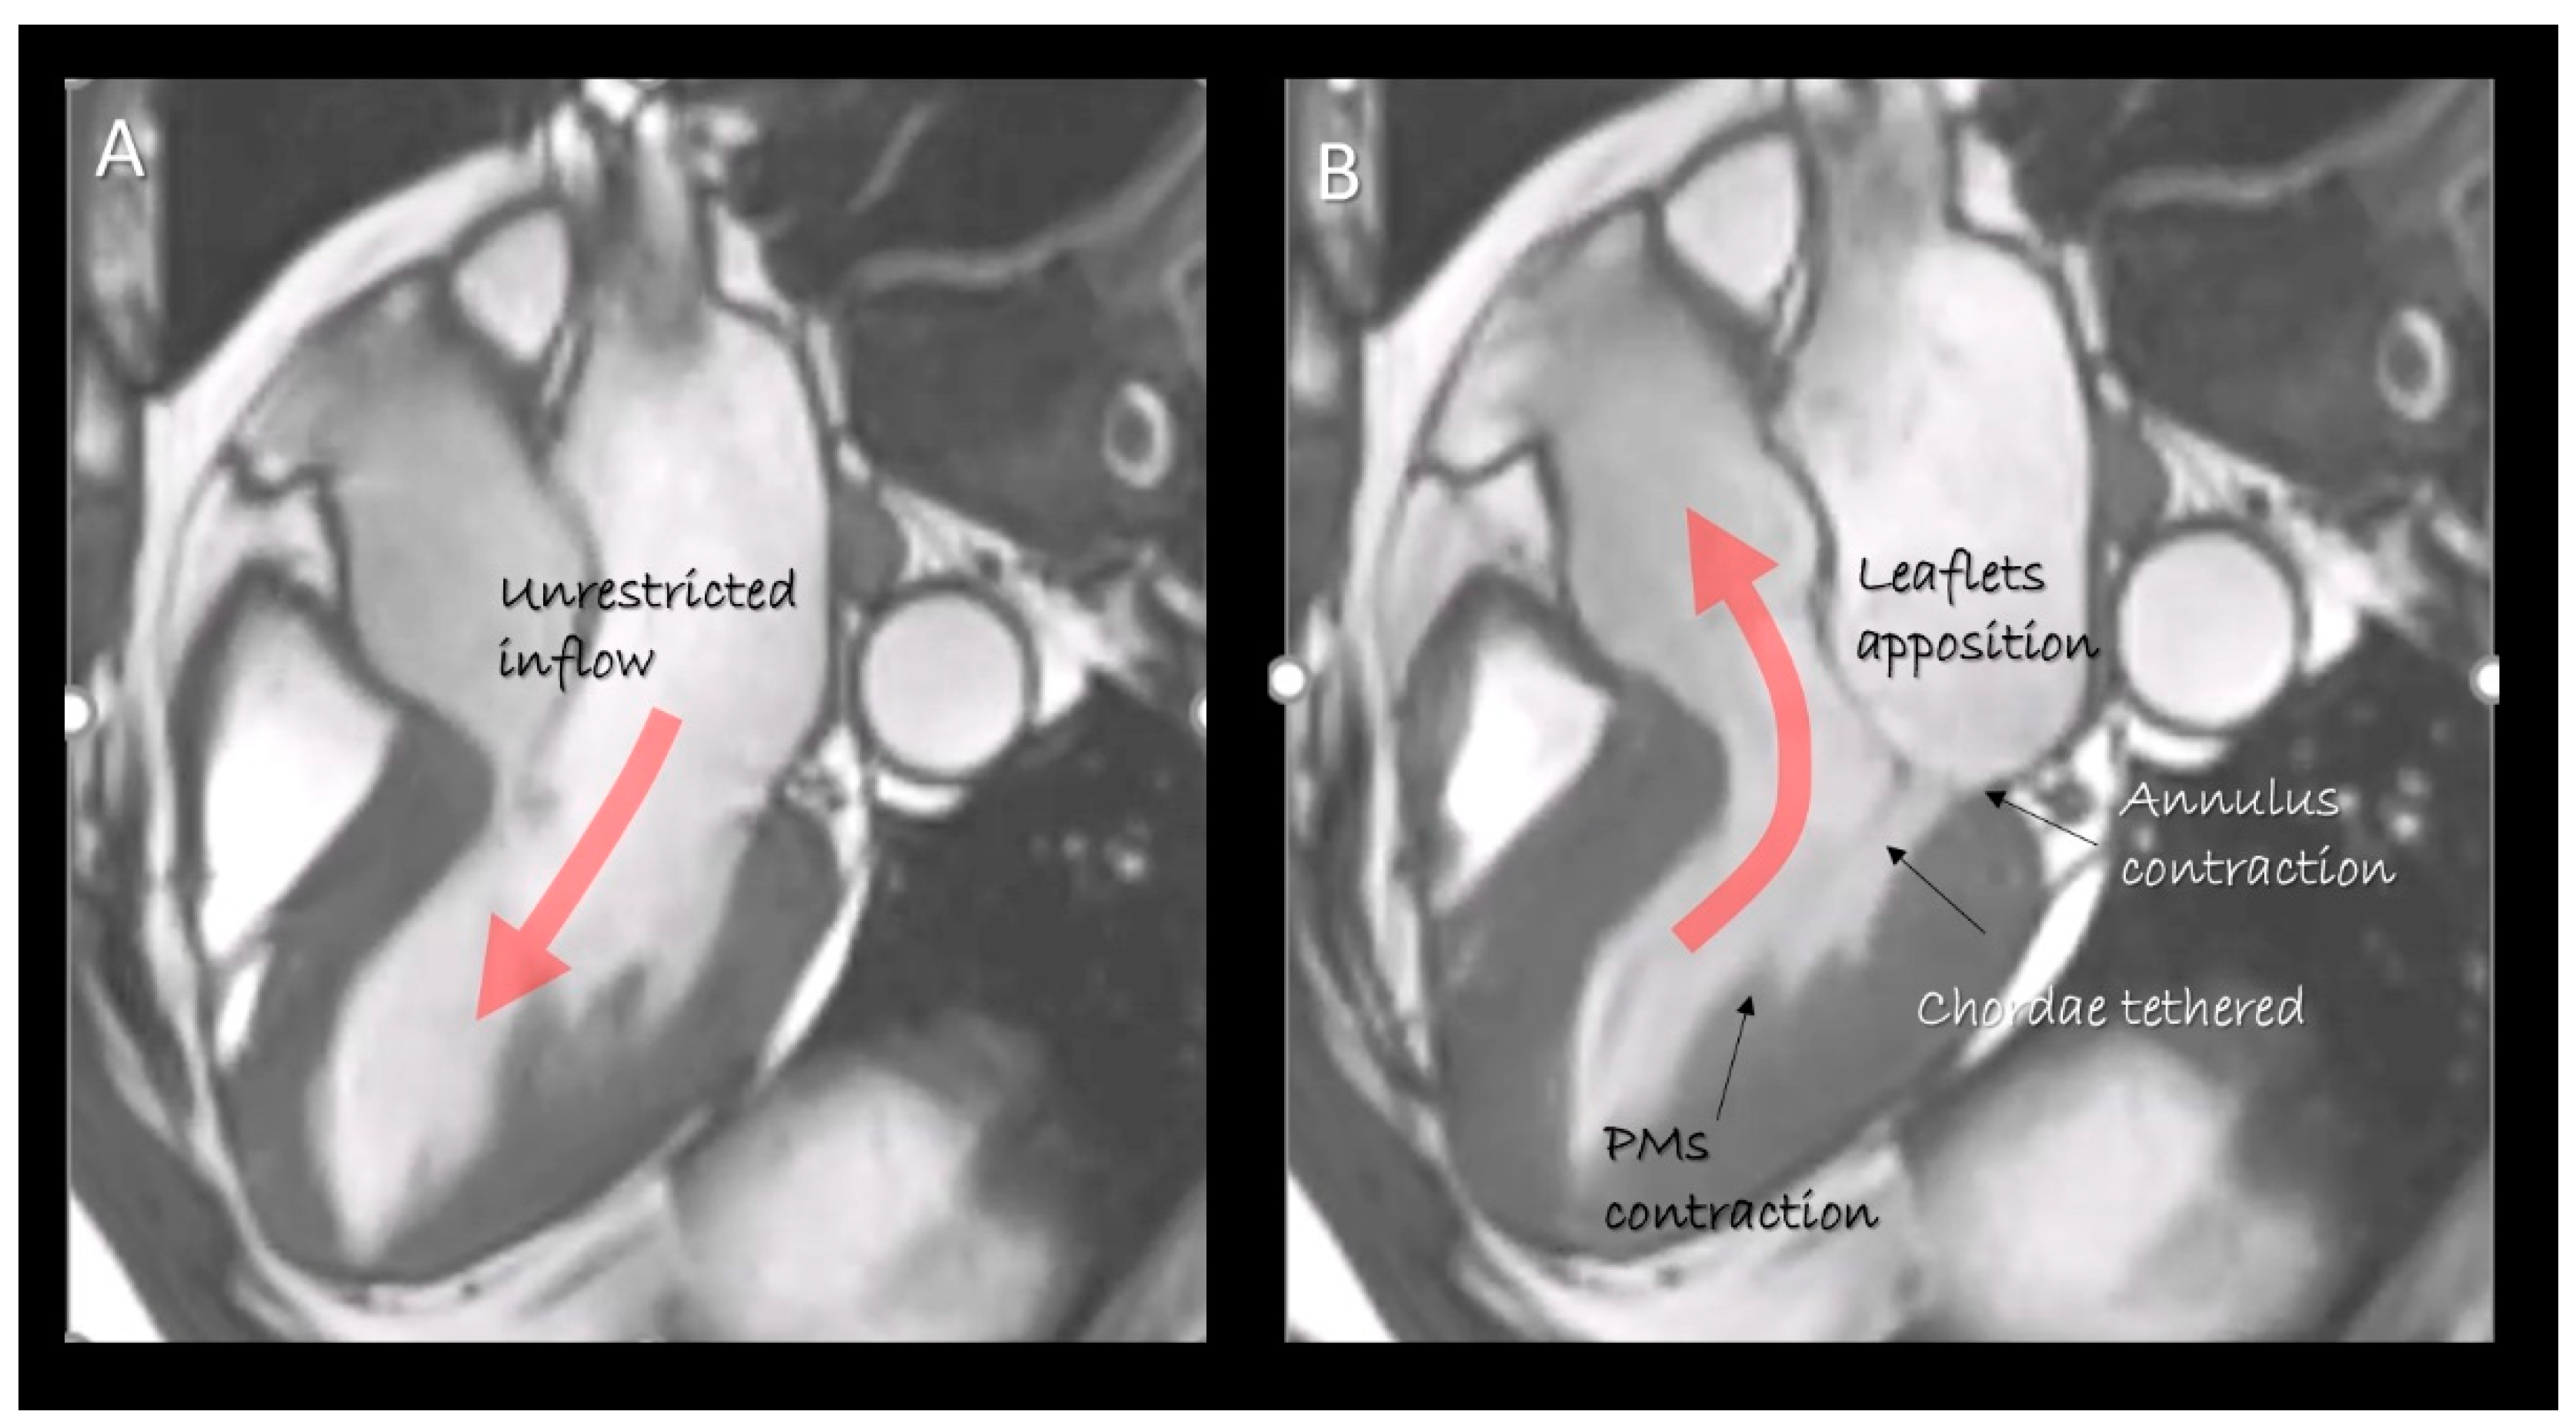

Figure 1.

Cardiac magnetic resonance (CMR) still frame image in cross-section long-axis view in (A) diastole and (B) systole showing the mitral valve apparatus formed by leaflets, annulus, chordae tendinea and papillary muscles. They move in a perfect spatial and temporal coordination to obtain an effective competence and an unrestricted inflow. The “dynamic” anatomy provided by non-invasive imaging techniques gives us the awareness as the structural arrangement of any single component serves to a specific function.

As emphasized by Perloff and Williams in their seminal paper [10], MV is not a mere couple of tissue flaps which open and close, following pressure fluctuations between the left atrium (LA) and the left ventricle (LV). On the contrary, the valve is a much more complex apparatus in which several components move in a perfect spatial and temporal coordination to ensure an effective valve competence and an unrestricted inflow. Key components of this dynamic three-dimensional apparatus are mitral annulus, leaflets, chordae tendineae and papillary muscles (PMs).

This review describes the anatomy of the components of the MV apparatus, as revealed by the aforementioned non-invasive imaging techniques, highlighting physiological, pathological, surgical and interventional implications related to specific anatomical structures (Figure 1).